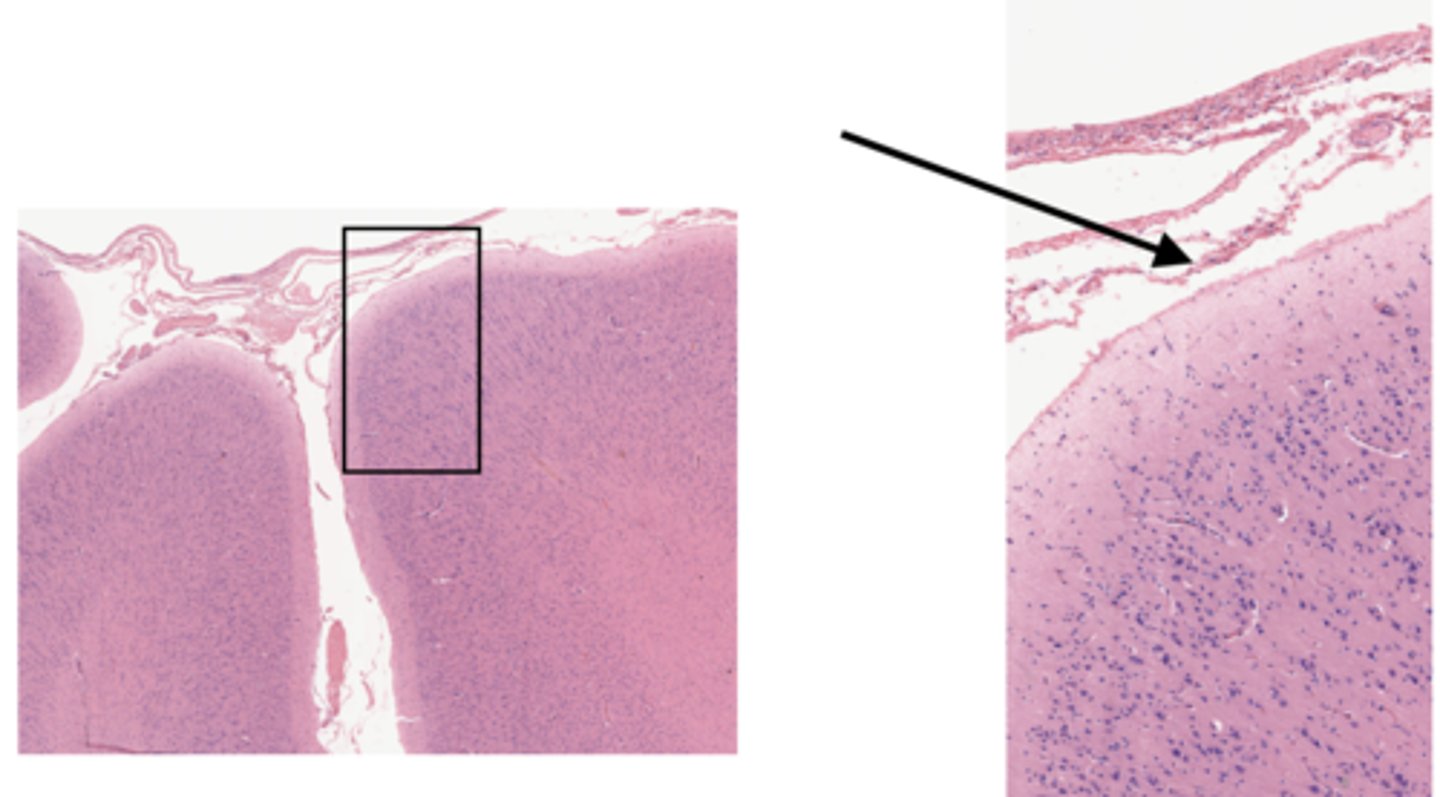

Identify the part of the spinal cord

dorsal funiculi

lateral funiculi

ventral funiculi

dorsal horn

ventral horn

dorsal root of spinal nerve

ventral root of spinal nerve

What is the midline structure that separates the dorsal left and right halves of the white matter

dorsal median septum

What is the midline structure that separates the ventral left and right halves of the white matter

ventral median sulcus

Identify the section of the spinal cord that contains nuclei

gray matter

Identify the section of the spinal cord that contains nerve tracts

white matter

central canal

Identify the part of the meninges

pia mater

arachnoid

dura mater